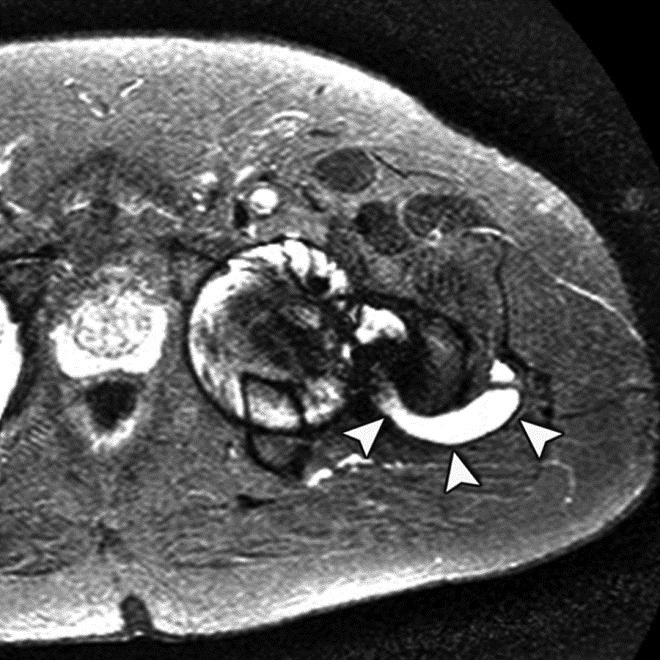

Adverse reaction to metal debris with posterior pseudotumor. Axial T1-weighted fast spin echo (FSE) (A) and STIR (B) MR images demonstrate left peritrochanteric fluid collection (arrow in A and arrowheads in B) arising from the left hip joint in a patient with metal-on-metal hip arthroplasty. Note the thin low T2 signal rim surrounding the fluid collection representing metal deposition. |

Adverse reaction to metal debris with anterior pseudotumor. Axial T1-weighted MR image shows large soft tissue mass (arrowheads) centered at the level of the lesser trochanter with involvement of the iliopsoas attachment site in a patient with metal-on-metal hip arthroplasty. Also note infiltrative involvement of the rectus femoris muscle.